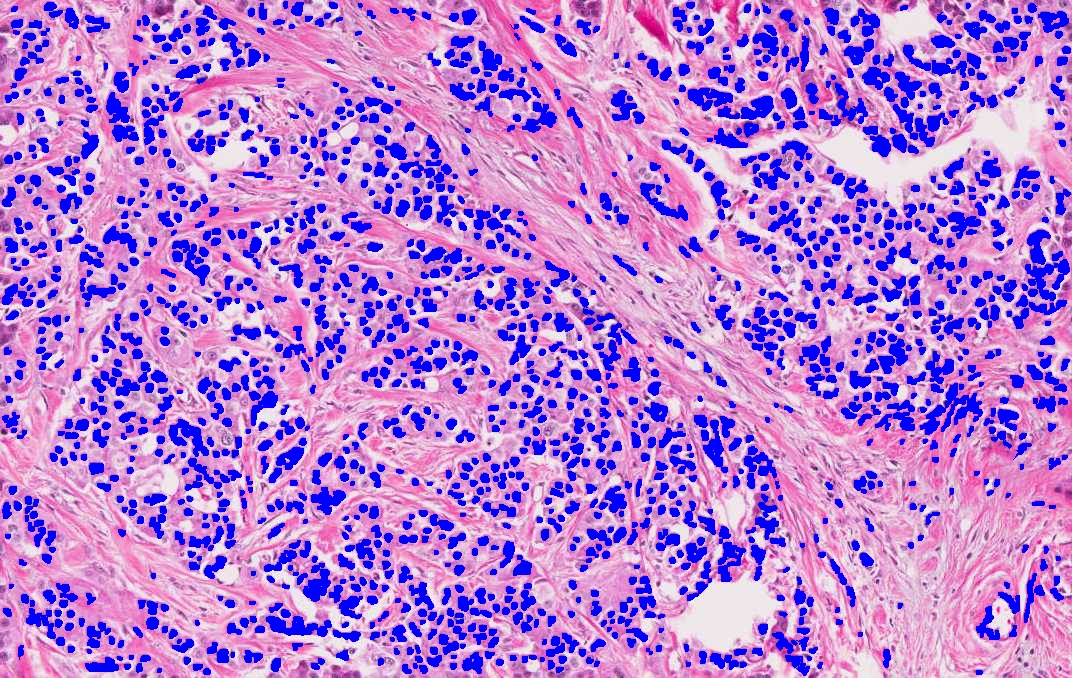

I used support vector machines (SVM) to develop a machine learning model that accurately predicts whether a breast cancer patient is likely to experience a recurrence after treatment. The prognosis method examines the patient's biopsy slide image with computer vision and leverages complex statistical methods to analyze the expression values of thousands of genes.